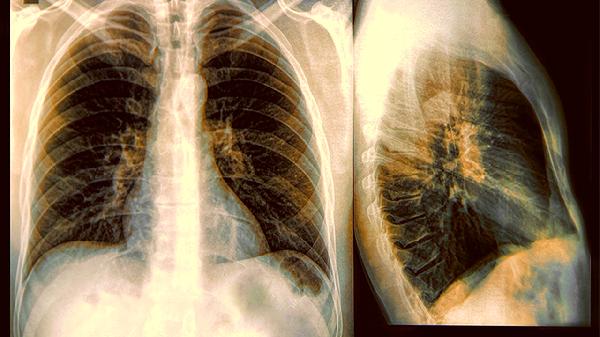

2.结节大小与风险的关系

一般来说,小于5mm的结节多为良性;5-10mm需要定期观察;超过10mm则需要进一步检查。新.闻中提到的8mm结节刚好处于需要密切关注的临界值。